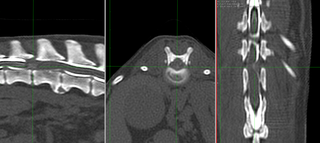

環軸不安定症 AAI

AAIとはヨークシャーテリア、チワワなどの超小型犬に発症する第一頚椎と、第二頚椎の不安定性による頸髄の障害です。通常、頚部痛、四肢不全麻痺などの症状がでます。

悪化すれば呼吸停止により突然死することもあります。